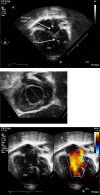

This review article will guide the reader through the basics of echocardiographic assessment of congenital left to right shunts in both paediatric and adult age groups. After reading this article, the reader will understand the pathology and clinical presentation of atrial septal defects (ASDs), ventricular septal defects (VSDs), atrioventricular septal defects (AVSDs) and patent arterial duct. Echocardiography is the mainstay in diagnosis and follow-up assessment of patients with congenital heart disease. This article will therefore describe the echocardiographic appearances of each lesion, and point the reader towards specific features to look for echocardiographically.